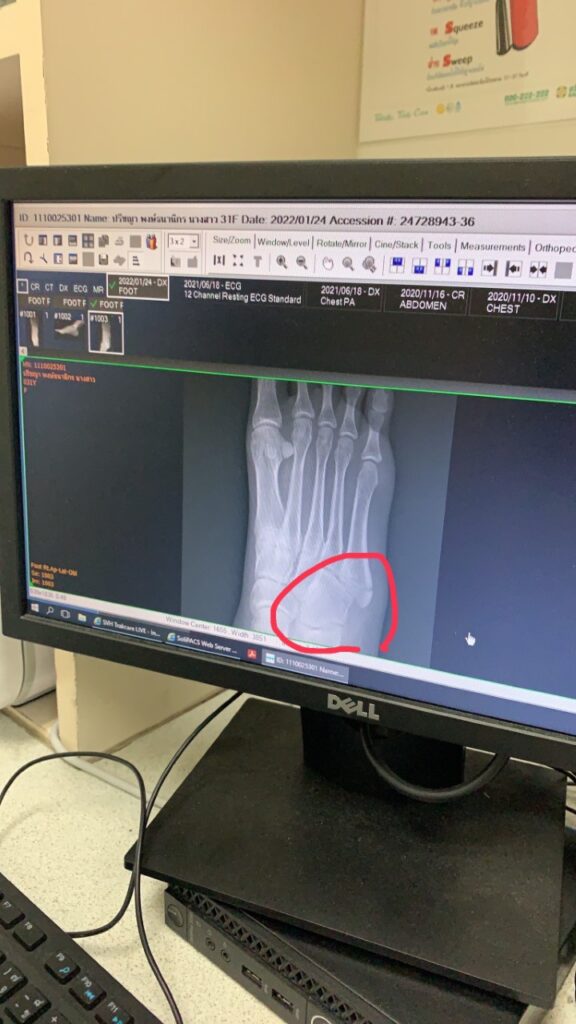

รู้แล้ว! “ไอซ์-ปรีชญา” กระดูกข้อเท้าหัก เกิดอุบัติเหตุกลางกองถ่าย เข้าโรงพยาบาลกลางดึก

จากเมื่อคืน(24 ม.ค.65) นางเอกสาว “ไอซ์-ปรีชญา พงษ์ธนานิกร”ได้รับอุบัติเหตุระหว่างถ่ายทำละคร “ศึกเสน่หาไกรทอง-ชาละวัน” ทางสถานีโทรทัศน์ช่อง8 ซึ่งเป็นฉากที่ไอซ์ กำลังคิดถึงหนุ่ม “โอห์ม-ฐิติวัฒน์” และกำลังจะทิ้งสร้อยแทนใจของหนุ่มโอห์ม ในระหว่างนั้นขณะที่เดินเข้าฉากได้ตกหลุมลึก ทำให้ข้อเท้าพลิก เกิดอาการปวดบวมจนไม่สามารถเดินและถ่ายทำละครต่อได้ ทางทีมงานละครเลยรีบส่งสาวไอซ์ไปโรงพยาบาลสมิติเวช สุขุมวิท เป็นการด่วน ซี่งผลตรวจจากหมอและผลเอกซเรย์พบว่า กระดูกข้อเท้าหัก และต้องดามเฝือกอ่อนไว้ก่อน  เบื้องต้นหมอที่รักษาแนะนำให้สาวไอซ์พักงาน 6-8 สัปดาห์ จนกว่ากระดูกจะเข้าที  งานนี้ฝากแฟนๆให้กำลังใจสาวไอซ์กันด้วยนะจ๊ะ